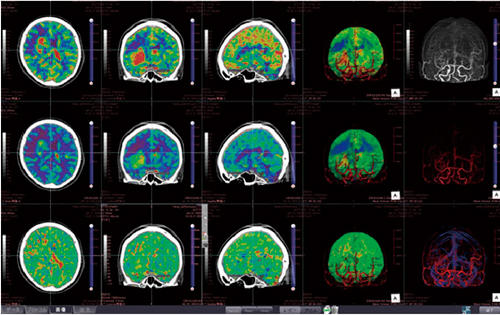

Area Detector CTやDual Source CTに代表されるような近年のCT装置の高性能化によって,経時的にボリュームデータを取得でき,全脳の血流解析が可能になりました。“CT脳血流解析(4D)”では,CBV,CBF,MTTの解析結果に血管のVR像を重ね合わせることで,病変や虚血領域,血管の位置関係などの把握が可能です。脳表の観察だけでなく,任意断面からの観察も可能なので,3次元的に灌流異常領域を把握できます。

さらに,CT脳血流解析(4D)では,これまで当社ワークステーションで用いられてきたパフュージョンやサブトラクション,自動抽出といった実績のあるアルゴリズムを利用するため,アプリケーション自体の解析や動作の信頼性も保証されています。脳の実質および血管の走行状態に加えて,パフュージョンのカラーマッピングの状態を,任意の方向または断面でリアルタイムに観察することが可能です。 また,豊富なレイアウト構築機能により,さまざまな画像レイアウトの表示が可能です。

CT脳血流解析(4D)